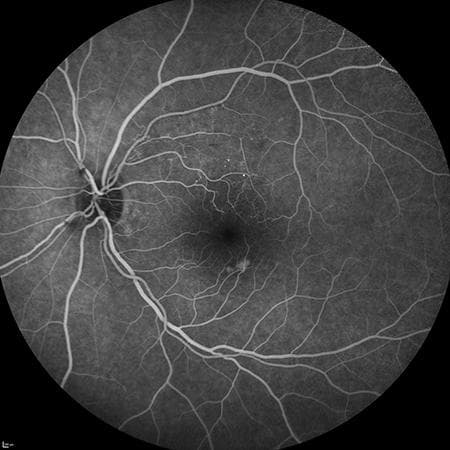

Angiografía retinal

Estudia la circulación de la retina y puede detectar fugas, obstrucciones o daño vascular en retinopatía diabética, mácula o trombosis retinal.

Angiografía retinal con fluoresceína